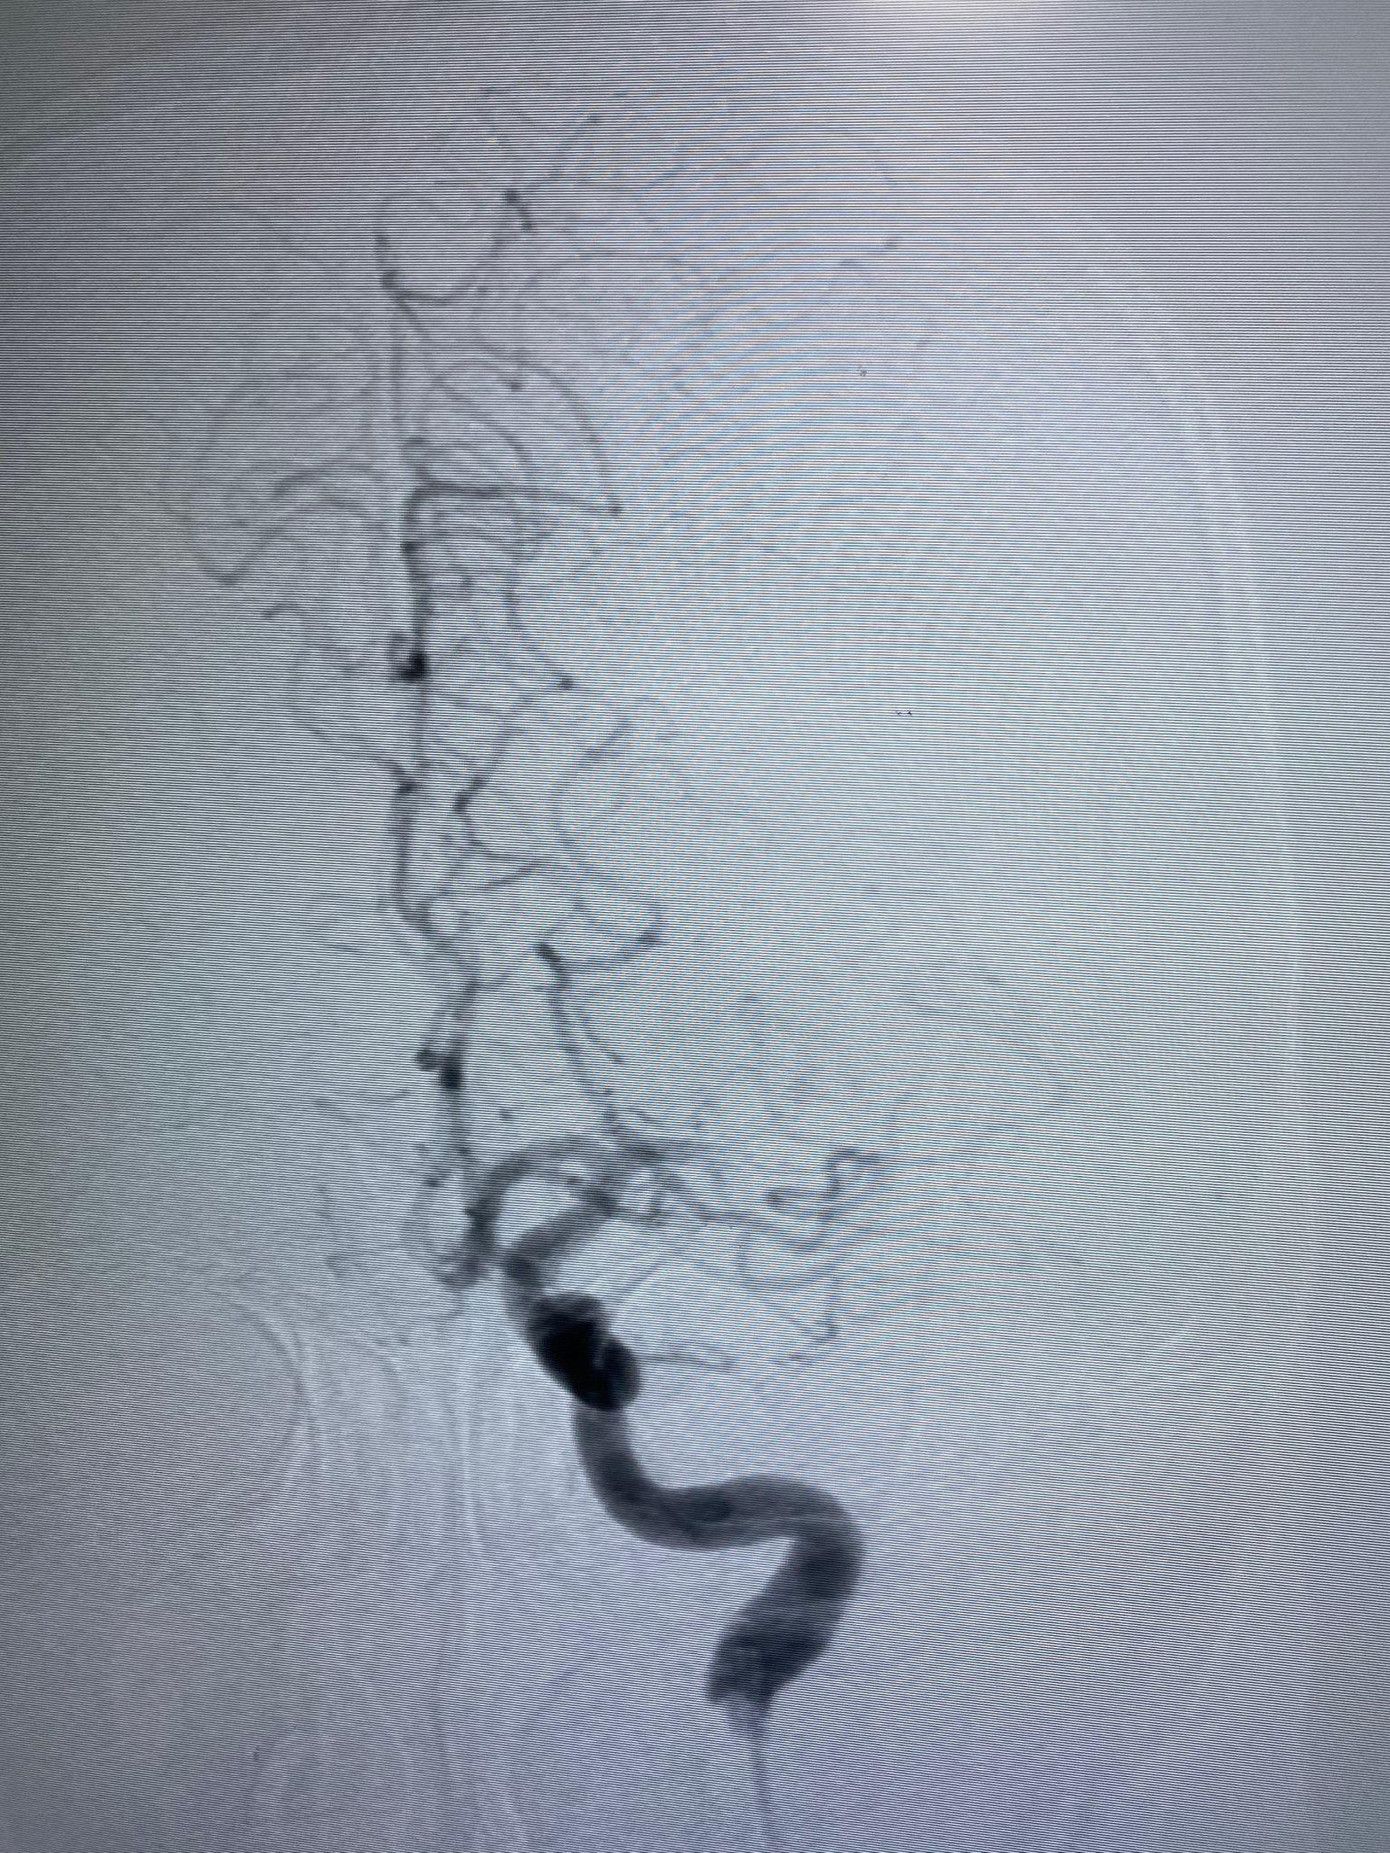

| Động mạch não giữa bên trái của bệnh nhân bị tắc thời điểm nhập viện cấp cứu |

Tại bệnh viện, sau khi thăm khám, các bác sĩ chẩn đoán bệnh nhân bị đột quỵ cấp nên lập tức kích hoạt quy trình cấp cứu đột quỵ, huy động liên chuyên khoa phối hợp chuyên môn. Theo BS Phạm Định Chương, Đơn vị Đột quỵ, trên hình ảnh MRI sọ não của người bệnh ghi nhận tình trạng nhồi máu não bán cầu trái, tắc động mạch não giữa bên trái.